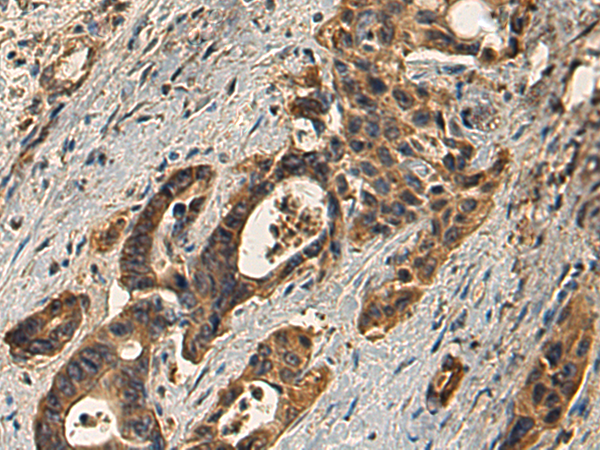

分类: 科研抗体货号: P02100别名:应用: WB,IHC反应种属: Human, Mouse